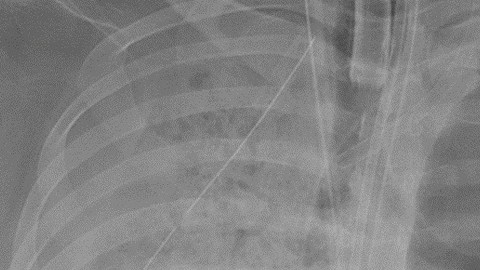

El daño en los pulmones era irreversible. Crédito: Northwestern Medicine | Cortesía

Según la información, la paciente pasó seis semanas en un respirador artificial. Pudo recuperarse del coronavirus, pero el daño en los pulmones era irreversible. La mujer fue puesta en la lista para transplantes, pero la operación solo era autorizada si una nueva prueba de COVID-19 era negativa.